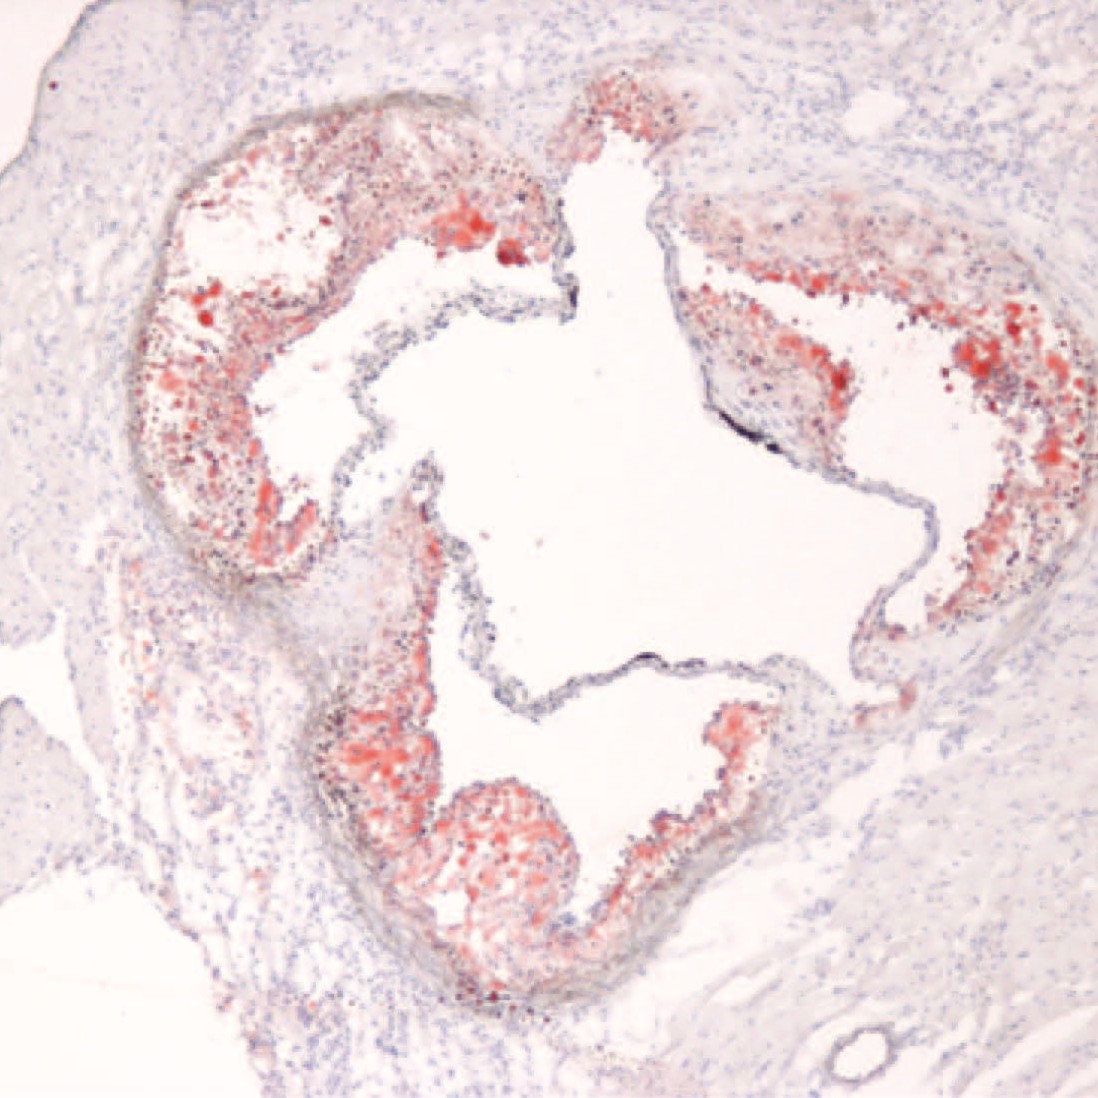

Inflammation, Immune Training and Atherosclerosis

Inflammation is a central pathogenic mechanism that drives atherosclerosis. Our group has identified that BET bromodomain-containing proteins—bona fide transcriptional coactivators—regulate the inflammatory cell state in atherosclerosis.

More recent work has identified that synergy between cytokine signaling pathways is dependent on BET bromodomain function. A major focus now is understanding how chronic inflammation is activated by CV risk factors such as hypertension and hypercholesterolemia through a process involving trained immunity.